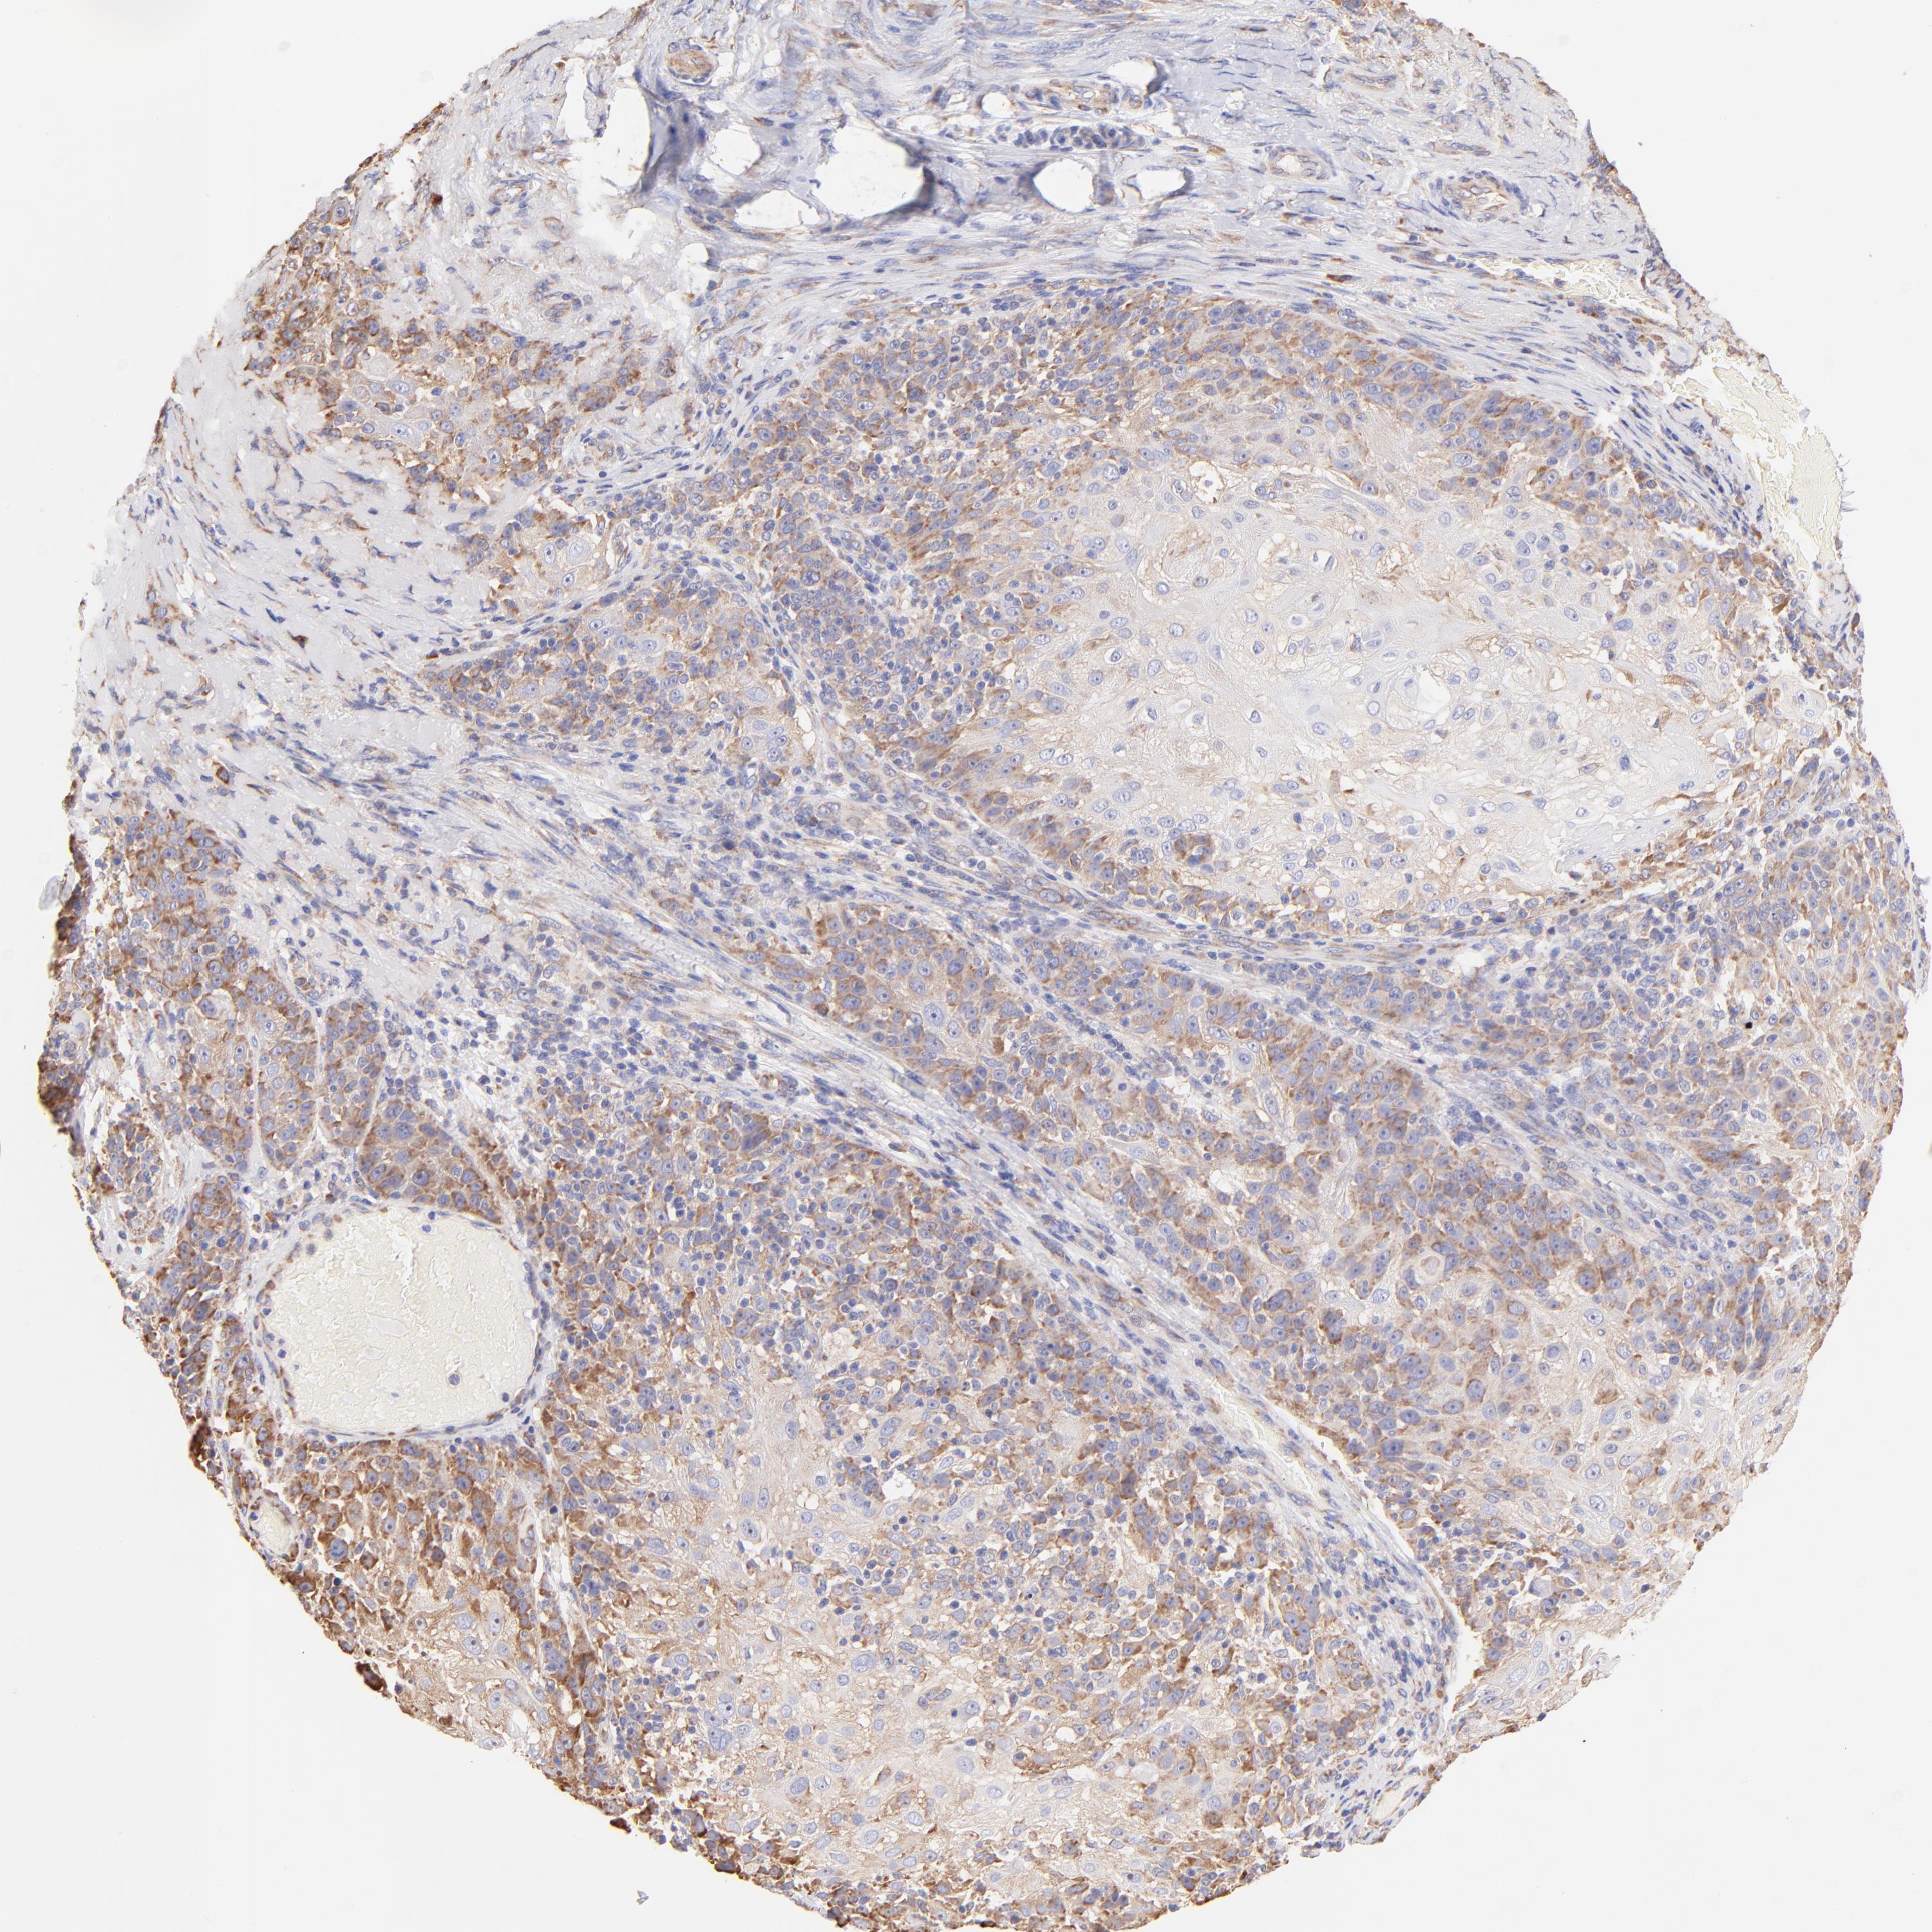

SKIN CANCER - Protein expressioni

A mouse-over function shows sample information and annotation data. Click on an image to view it in a full screen mode. Samples can be filtered based on level of antibody staining by selecting one or several of the following categories: high, medium, low and not detected. The assay and annotation is described here.

Antibody stainingi

Antibody staining in the annotated cell types in the current human tissue is reported as not detected, low, medium, or high, based on conventional immunohistochemistry profiling in selected tissues. This score is based on the combination of the staining intensity and fraction of stained cells.

Each image is clickable and will lead to virtual microscopy that enables deeper exploration of all samples and also displays staining intensity scores, fraction scores and subcellular localization as well as patient and tissue information for each sample.

Antibody HPA002651

Staining

High

Medium

Low

Not detected

Intensity

Strong

Moderate

Weak

Negative

Quantity

>75%

75%-25%

<25%

None

Location

Nuclear

Cytoplasmic/membranous

Cytoplasmic/membranous,nuclear

Basal cell carcinoma